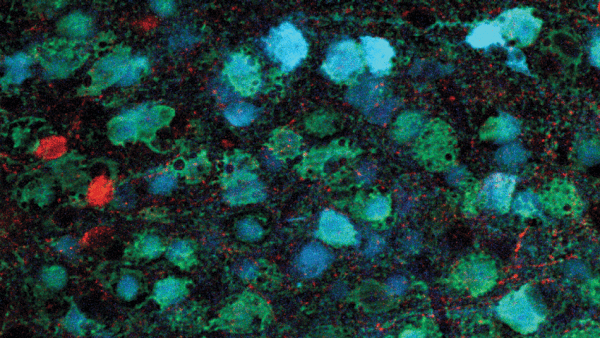

Archive: Building a Patchwork Brain to Study Neurological Disease

Archive: New Immunotherapy for Deadly Childhood Brain Cancer Targets Novel 'Neoantigen'